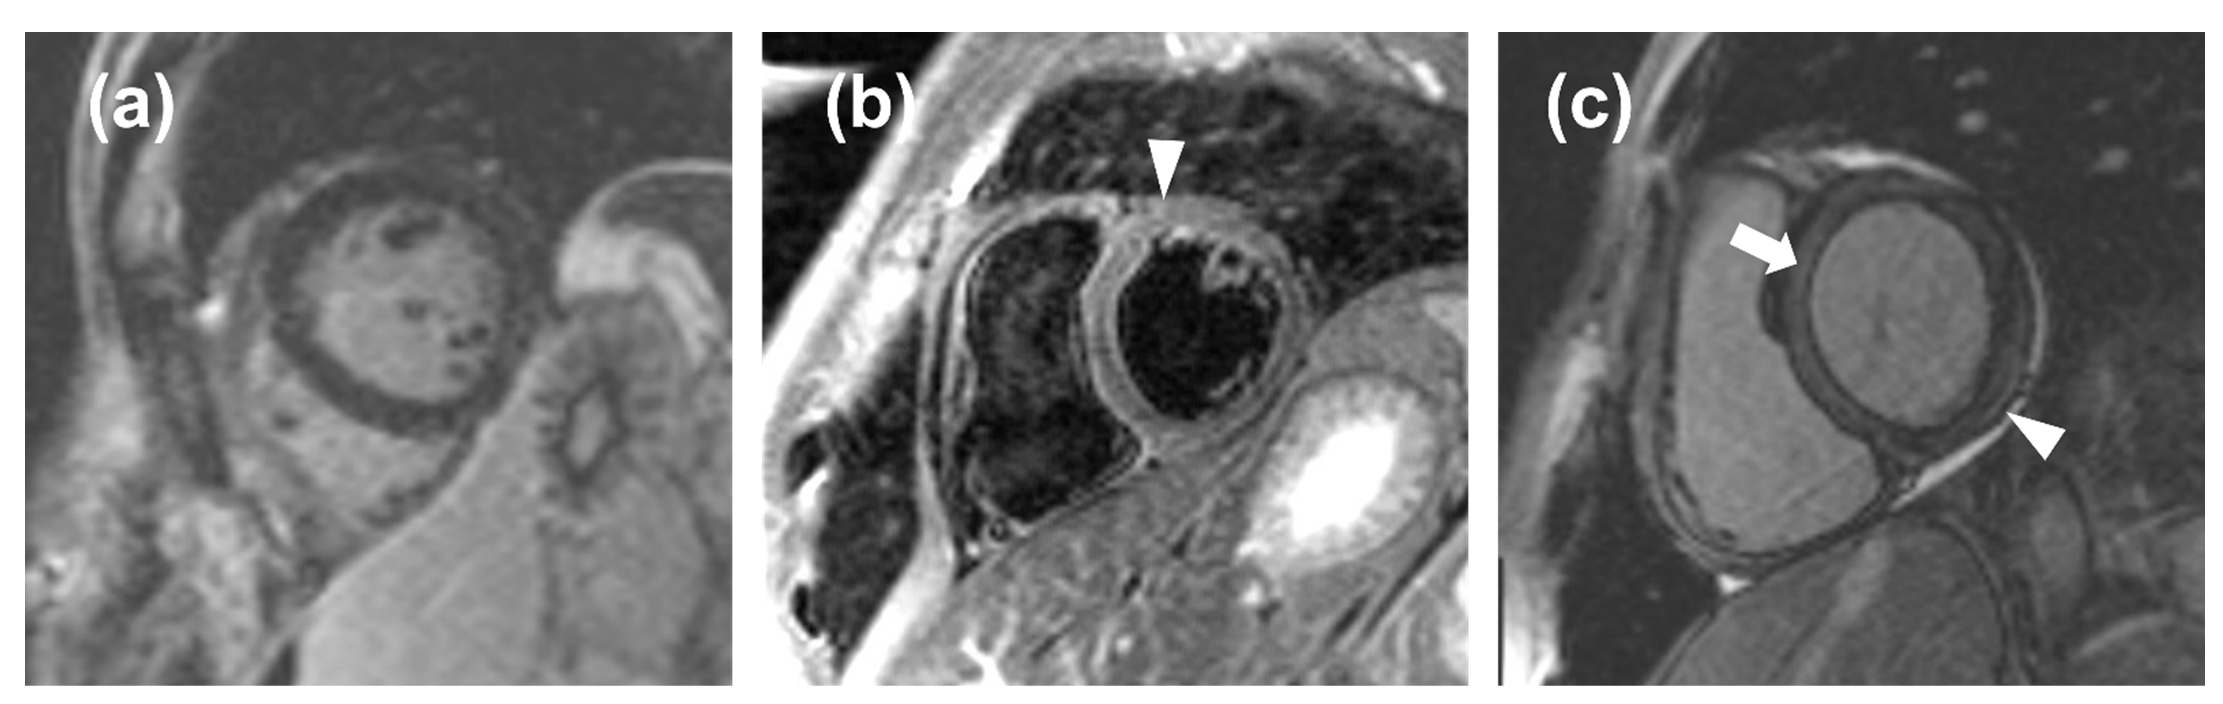

The ROC curve obtained from LGE data from acute-phase patients and controls has a moderate area under the curve, resulting in an optimal threshold of 5% with a high value of sensitivity (87%) but low specificity (48%). Indeed, minimal LGE appears most commonly as a thin, subepicardial line, easily mistaken for adipose tissue, that the software cannot assess with sufficient accuracy, resulting in a falsely negative assessment (Figure 5). This means that quantitative LGE evaluation may be useful for excluding myocarditis in patients testing negative for our threshold, with a negative likelihood ratio of 0.27, which indicates that a negative LGE test determines a reduction of the post-test probability of the disease by 73% as compared to the pre-test probability [21]. Hence, LGE could be used as a quantitative criterion, albeit with certain limitations with regards to its specificity and visual assessment. Our LGE values are lower than those obtained by Ferreira et al. [19] for both acute-phase patients (11%, IQR 5% to 21%) and controls (0%, IQR 0% to 2%), as well as those obtained by Luetkens et al. [22] at the acute phase (15.8 ± 12.0%) and follow-up (7.2 ± 5.9%), whereas our controls LGE values are similar to those reported by Luetkens et al. [22] for controls (4.8 ± 4.4%). Since LGE values for the acute phase and follow-up depend on disease severity, we should highlight that other studies did not exclude patients with a compromised ejection fraction, hence displaying higher values compared to ours, which were derived from patients with mild myocarditis with preserved ejection fraction.

Figure 5.

(a), a false negative case in which the noise masked the late gadolinium enhancement (LGE); (b), a false positive case in which the noise mimicked edema (arrowhead); (c), a false positive case in which an inaccurate inversion time caused a relative hyperintensity of the myocardium (arrow) that mimicked a thin, subepicardial band of LGE (arrowhead).